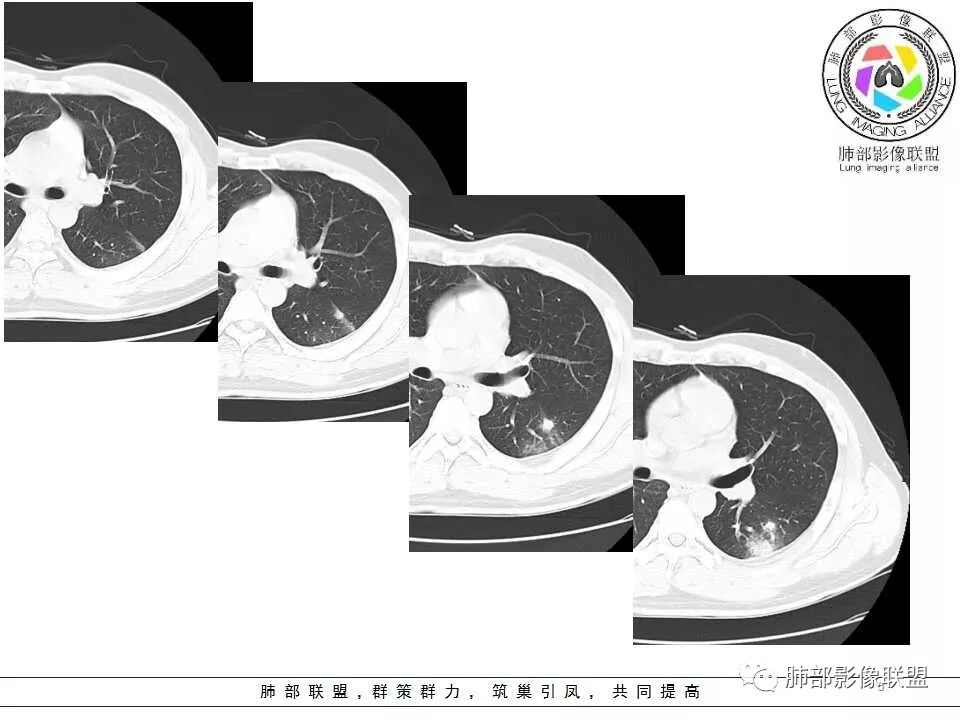

影像资料

左肺下叶肿块,密度不均,其内有低密度坏死,周围有晕,支气管进入阻塞,长轴平行胸膜,周围可见形态密度一致小病灶,考虑隐球菌。鉴别淋巴瘤。

青年男性,急性起病,左肺下叶近胸膜可见实变及结节影,宽基底与胸膜相连,胸膜下脂肪间隙可见,支气管部分中断,未见树芽,良性病变,考虑隐球菌可能,鉴别结核。

左肺下叶实变,长轴与胸膜平行,边缘平直、膨隆,周围有边缘模糊晕,近端支气管进入病灶,內有低密度坏死,邻近胸膜弥漫性增厚,胸膜外间隙增宽;病灶周围肺野有多个斑片,部分内有扩张小支气管。青年男性,病史10天,考虑炎性,1、隐球菌,2、TB。

青年男性,咳嗽、左侧胸痛10余天。血常规(一)。左下肺胸膜下见一肿块影,糊墙,长轴与胸膜平行(碰到胸膜往两侧走),近端支气管进入后堵塞,内有小片状低密度区,边缘见模糊的GGO。肿块周围见类似密度的小结节。综上考虑良性病变,隐球菌可能性大。

胸膜下,边缘平直,支气管进入后稍扩张,周边有晕,类似结节,横轴与胸膜平行,首先考虑隐球菌。

青年男性,左肺下叶实变影,长轴与胸膜平行,支气管进入后堵塞,边缘晕征,略膨隆,内有低密度影。结合病史,咳嗽,咳痰。考虑:炎性肉芽肿,隐球菌感染。建议检查隐球菌抗原、增强或穿刺活检。鉴别,淋巴瘤,肺链。

青年男性,左肺下叶背段实变,宽基底与胸膜相连,周围有晕,考虑炎性病变,隐球菌?TB?

青年男性,无发热,呼吸痛,体重下降。左肺下叶实变,宽基底,气管进入后截断,周边有模糊的晕,晕中带刺儿,内见多发小坏死,收缩为主,稍有膨隆,糊墙,多发病灶,支持隐球。

青年男性,以胸痛为主,左肺下叶胸膜下多发实变团块影,病灶相似,边缘有晕,部分边缘平直,胸膜糊墙,大病灶内可见支气管进入,远端阻塞,纵膈窗显示病变密度不均,首先考虑感染性病变,隐球菌可能大。

青年男性,咳嗽10余天,体检发现,左肺下叶胸膜下团块影,与支气管相通,内见坏死区,边缘长毛刺,有晕征,胸膜下脂肪间隙存在,周围见小结节影,常规考虑肉芽肿病变,隐球菌可能,结核待排,建议增强及抗炎后复查。

左肺下叶胸膜下肿块,密度不均,内见低密度坏死区,病灶边缘有膨隆,也有收缩,周围有晕,支气管进入近端阻塞,远端支气管走行通畅,病灶长轴平行胸膜,胸膜糊墙,周围可见多发类似结节,形态单一,考虑感染性病变,隐球菌?

青年男性,左肺下叶实变影,长轴与胸膜平行,支气管进入后闭塞略扩张,边缘晕征,略膨隆,内有低密度影,糊墙,周围小结节状小片状影类似,考虑炎性病变,隐球菌可能,不除外一般炎症并小脓肿形成,建议结合临床和隐球菌抗原检查。

中年男性,咳嗽胸疼,左肺下叶团片状影,边缘平直,内有多灶坏死,胸膜下分布,与胸膜宽基底相连,周围有晕及晕中毛刺,有卫星灶,支气管进入走行自然,有的穿过,有的近中段阻塞,胸膜下脂肪间隙清晰,考感染性疾病,隐球菌肺炎可能性大,鉴别op。

隐球菌+1,长轴平行胸膜、有晕,有蘑菇兄弟,支气管进入病灶后阻塞,边缘平直为主,广基底与胸膜相连。

青年男性,咳嗽,胸痛10天,白细胞不高,中性粒细胞不高,1月前有发热史,1年内体重下降10公斤,胸部CT所见左肺下叶跨背段及后基底段不规则形团块影,宽基底与胸膜相连,胸膜下脂肪间隙清楚(糊墙),长轴平行胸膜,内有坏死,边缘毛糙,周围见晕征,病灶旁有斑点状及小结节状影,病灶由外向内包绕支气管,考虑:炎性肉芽肿,隐球菌可能,结核待排,查隐球菌荚膜实验,必要时痰检及结核相关检查。

男性,29岁。咳嗽伴左侧胸痛10余天,吸气时胸痛加重,无发热/咳血盗汗。左肺下叶背段斑片样阴影,部分边缘欠清,周围可见小片状偏高密度影,近胸膜面分布。支气管进入病灶内,感觉走形较柔软,主体病灶长轴与支气管垂直,壁层胸膜下脂肪间隙可见,病灶内似可见更低密度影。结合临床,考虑炎性病变,隐球可能性大,结核抗体弱阳性,还是要待排的。

左肺下叶胸膜下片状高密度影,密度均匀,近端支气管进入后阻断,形态欠规则,边缘GGO模糊,病灶长轴与胸膜平行,与相邻胸膜呈糊墙改变,相应胸膜增厚,考虑炎性病变,隐球菌可能性大。

青年男性,急性病程,右肺下叶背段块影,宽基底与胸膜相连,胸膜下脂肪间隙清晰,支气管有近端截断,远段有贯通,密度均匀,边缘有模糊的晕,附近有类似小病灶,考虑感染,隐球菌。

左肺下叶胸膜下多发病灶,支气管进入有堵塞,长轴平行胸膜,糊墙,考虑炎性病变可能性大 ,隐球菌首先考虑。待排粘液腺癌。

青年男性,左肺下叶团片影,支气管进入有堵塞,病灶边缘有晕,周围散在相似小病灶,病灶胸膜平行,考虑炎性病变,隐球菌?

左肺下叶胸膜下肿块,支气管进入有堵塞,长轴平行胸膜,内部有坏死,考虑炎性病变 ,考虑隐球菌。

青年男性,咳嗽咳痰胸痛,有发热史,体重下降,结核抗体弱阳性。胸部CT所见左肺下叶跨背段及后基底段不规则形团块影,边界相对清楚,内部似见坏死,病灶沿胸膜下平行于胸膜横向发展,邻近胸膜增厚,周围见边界不清磨玻璃密度影。左肺下叶背段及后基底段近肋膈角区见多发较小形态及密度相似结节,部分结节周围见条索影。综合考虑炎性病变,隐球菌感染可能性大,建议查隐球菌荚膜实验,询问有无鸽子接触史等。

青年男性,咳嗽无发热,结核抗体阳性,体重下降明显,CT影像示左肺下叶团片状高密度灶,形态欠规整,周围见斑点片状卫星灶,病灶中心部分坏死,宽基底与胸膜相连,支气管穿行,管壁光滑,远端似见闭塞,余肺未见明显异常,倾向考虑感染性病变。